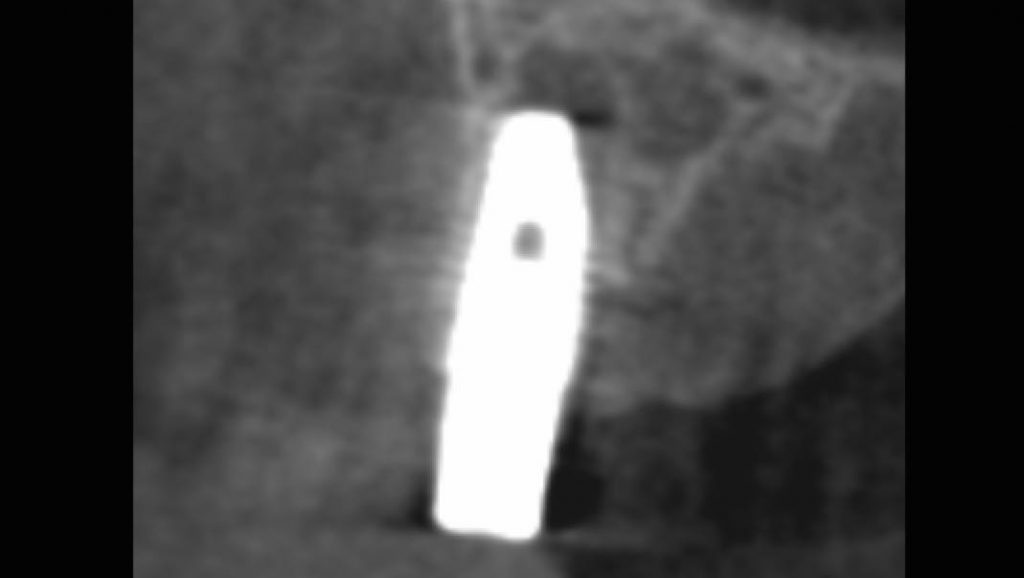

Non-Invasive Removal of Abutment and Dental Implant in the Aesthetic Zone

Removal of a dental implant with bone loss and poor position resulting in compromised aesthetics and appearance; Demonstration of how an implant can be removed with no incision or bone removal, even in circumstances where the implant has been in place for years and fully integrated.